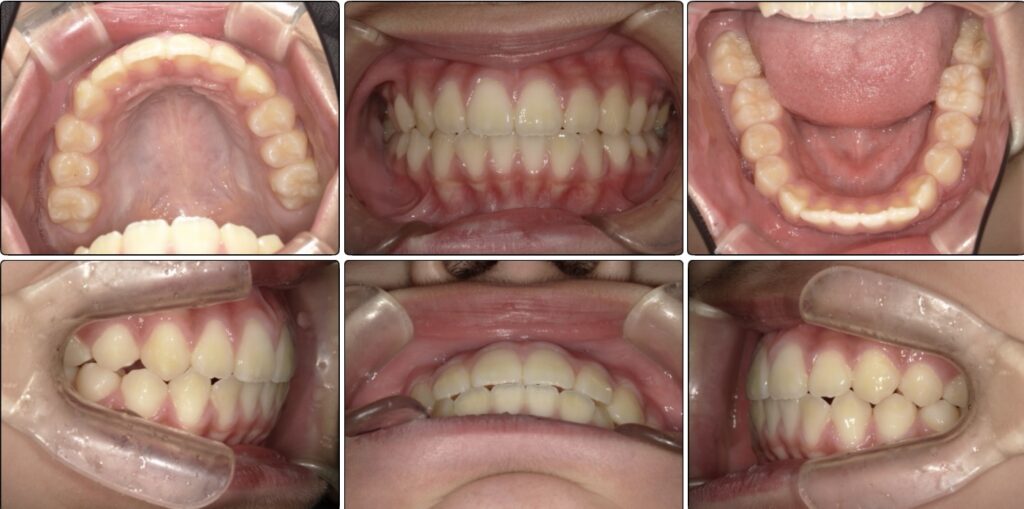

上顎の成長は舌が鍵になる!!

舌のアクティビティでは舌の先でスポットに触る感覚が難しく、舌先を巻いてしまっていました。

舌先の感覚を養うのに苦戦していましたが、感覚を掴めてからはスムーズに舌のアクティビティも嚥下のアクティビティも進んでいくことができました。

犬歯の生え変わりのタイミングで上の顎にBWS という装置を2ヶ月使用しました。

BWS をしている時期は少し歯の間に隙間ができることがありますが、

マウスピースの装着、口を閉じること、いつもスポットに舌を置くこと、歯を噛んでおくことを意識してくれているとその後しっかりと歯は噛み合ってきます。

しっかりと意識してくれていたので骨自体が前方成長できています!!